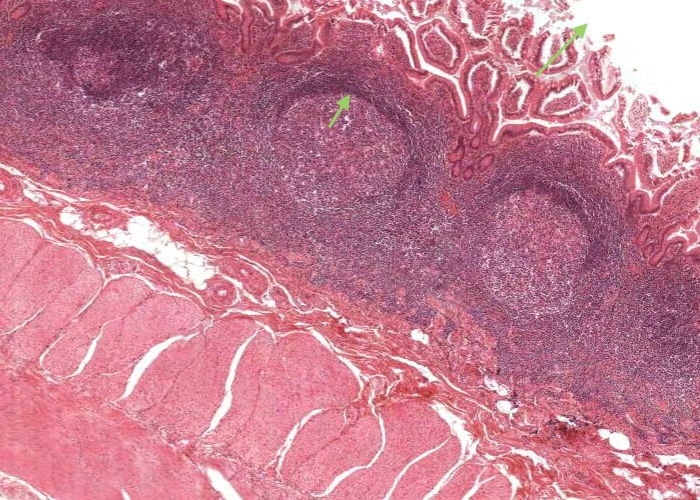

This image of the ileum shows the aggregation of lymphatic nodules known as Peyer’s patches. These are a component of the gut associated lymphatic tissue (GALT) and their function in relation to the small intestine presumably parallels that of the tonsil to the pharynx and the appendix to the colon.

Note that the corona has more lymphocytes around one side than the others. The more developed side is towards the lumen, as it also is for the appendix. It is uncertain whether or not these three lymphatic aggregations along the gastrointestinal tract have some special role in immunity beyond those of isolated nodules found throughout the mucosae of the body. They of course enable you to readily identify the ileum from other segments of the small intestine such as the duodenum and jejunum which you will learn more about in a later topic.

The appendix represents a small blind outpocketing of the large intestine. The mucosal and submucosal layers have been entirely converted into a mass of lymphoid tissue. Note the similarity in structure between the appendix and the tonsil. Both contain enormous depots of lymphoid tissue separated from a dirty, stagnant space or lumen by an epithelium infiltrated with lymphocytes. Tonsils alert the immune system to the resident bacteria in the throat. The appendix stimulates immunity to the range of bacteria that colonize the other end of the GI tract.

The mucosal layer and submucosal layer have been entirely converted into a mass of lymphoid tissue. Only the muscularis externa is a clearly recognisable typical layer of the gut wall.

Enormous depots of lymphoid tissue within the mucosa and submucosa are separated from a stagnant lumen by an epithelium infiltrated with lymphocytes.